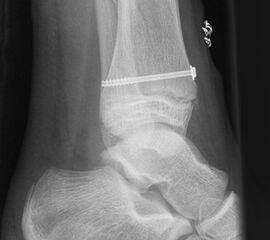

Ist die korrekte Stellung nur gegen einen federnden Widerstand zu erreichen, kann die Fraktur durch perkutane K-Drähte stabilisiert werden. Bei einer Fugenschaftfraktur mit großem Keil ist auch eine Schraubenosteosynthese möglich (Abbildungen 13 bis 14).

Behandlungsziel ist die exakte Rekonstruktion der Gelenkfläche sowie die Minimierung des Risikos einer späteren Wachstumsstörung. Dislozierte Frakturen werden offen reponiert, die Osteosynthese erfolgt mit einer Kleinfragmentschraube. Finden sich viele kleine Fragmente kann eine K-Draht Osteosynthese durchgeführt werden. Wird der Innenknöchel operiert, kann bei gleichzeitiger hochgradiger lateraler Instabilität eine Rekonstruktion des lateralen Bandapparats durchgeführt werden. Fibula Frakturen stellen sich meist spontan ein, sodass hier keine zusätzliche Osteosynthese notwendig ist.